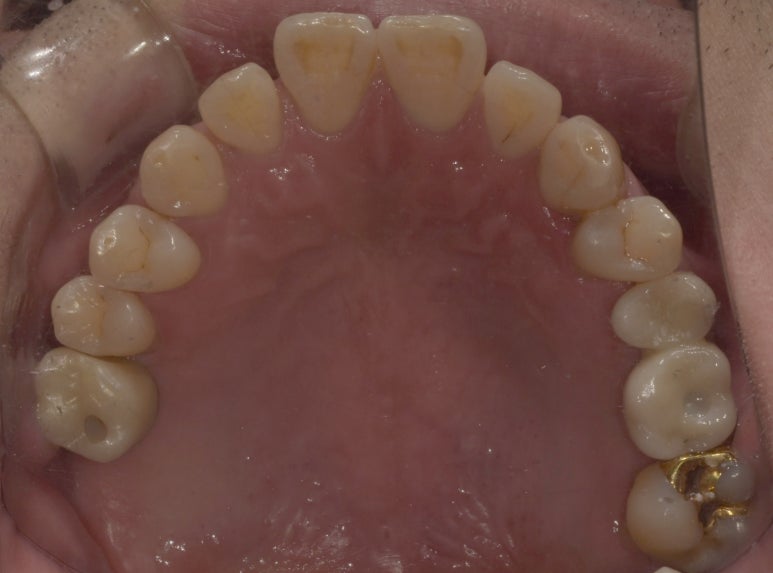

실제 구내 사진을 함께 보실까요?

임플란트 수술 전후

(전) 2022-04-28 (후) 2023-04-06

사진을 보시면 특히 #26 같은 경우는 육안으로 보기에도 치아 뿌리가 노출되는 등

임플란트가 시급한 상태였는데, 치료 후에는 제자리에 치아가 잘 자리잡고 있는 것을 확인할 수 있습니다.